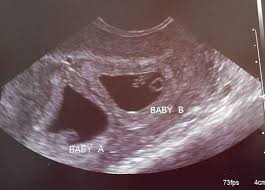

Twins 6 Week Ultrasound / The Ultrasound That Changed Everything / The unborn twins in china were seemingly hitting each other as their mother underwent a scan at four months pregnant.. Some need them more often. Father was amused to see his unborn girls seemingly. Ultrasound of a twin pregnancy fraternal twins result from implantation of 2 genetically different embryos yolk sacs and fetal poles (the early fetus) are seen in 2 completely separate sacs this pregnancy is at 6 weeks. The doctor pointed out the shared outer sac (chorion) and the two distinct inner sacs (amnions). It really amazes me that this happens as much as it does.

Belly pictures, symptoms & ultrasound. An early ultrasound can be helpful if you're not sure of. 6 weeks pregnant with twins belly pictures. Ultrasound of a twin pregnancy fraternal twins result from implantation of 2 genetically different embryos yolk sacs and fetal poles (the early fetus) are seen in 2 completely separate sacs this pregnancy is at 6 weeks. Reader noura i was kind enough to share ultrasound images of her di/di identical twins, whose ultrasounds look just like those of fraternal.